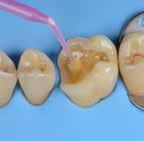

Why immediate dentine sealing?

Resin infiltration into the dentine surface is more effective on freshly cut dentine because it is uncontaminated and clean. Immedciate Dentine Sealing protects dentine against contamination with bacteria or remnants of temporary cements. It prevents post-operative sensitivity by sealing dentine tubules. It increases bond strength of the final indirect restoration to the tooth. It often eliminates the need for anaesthesia during the cementation procedure (when the restoration is delivered in the next appointment).

Tips and Tricks

• Placing a rubber dam and isolating neighbouring teeth with teflon tape are always recommended.

• Use maximum air pressure to dry 1-PRIMER of G2-Bond to remove the solvent & residues of water.

• 1-PRIMER should be kept out of light as it contains photoinitiators.

• When doing immediate dentine sealing with G-Premio BOND, it is recommended to add a thin layer of G-aenial® Universal Injectable or a flowable composite on top.

1. Clean the tooth surfaces, rinse thoroughly and dry Apply G-Premio BOND Apply 1-PRIMER of G2-BOND Universal

5. Air dry to make a uniform bonding layer

4. Light cure

5. Fill in the undercuts with everX Flow®. Perform deep margin elevation if needed.

6. Remove unpolymerized layer. Expose enamel covered with adhesive with a fine grit diamond bur.

2A. G-Premio BOND

2B. G2-BOND Universal